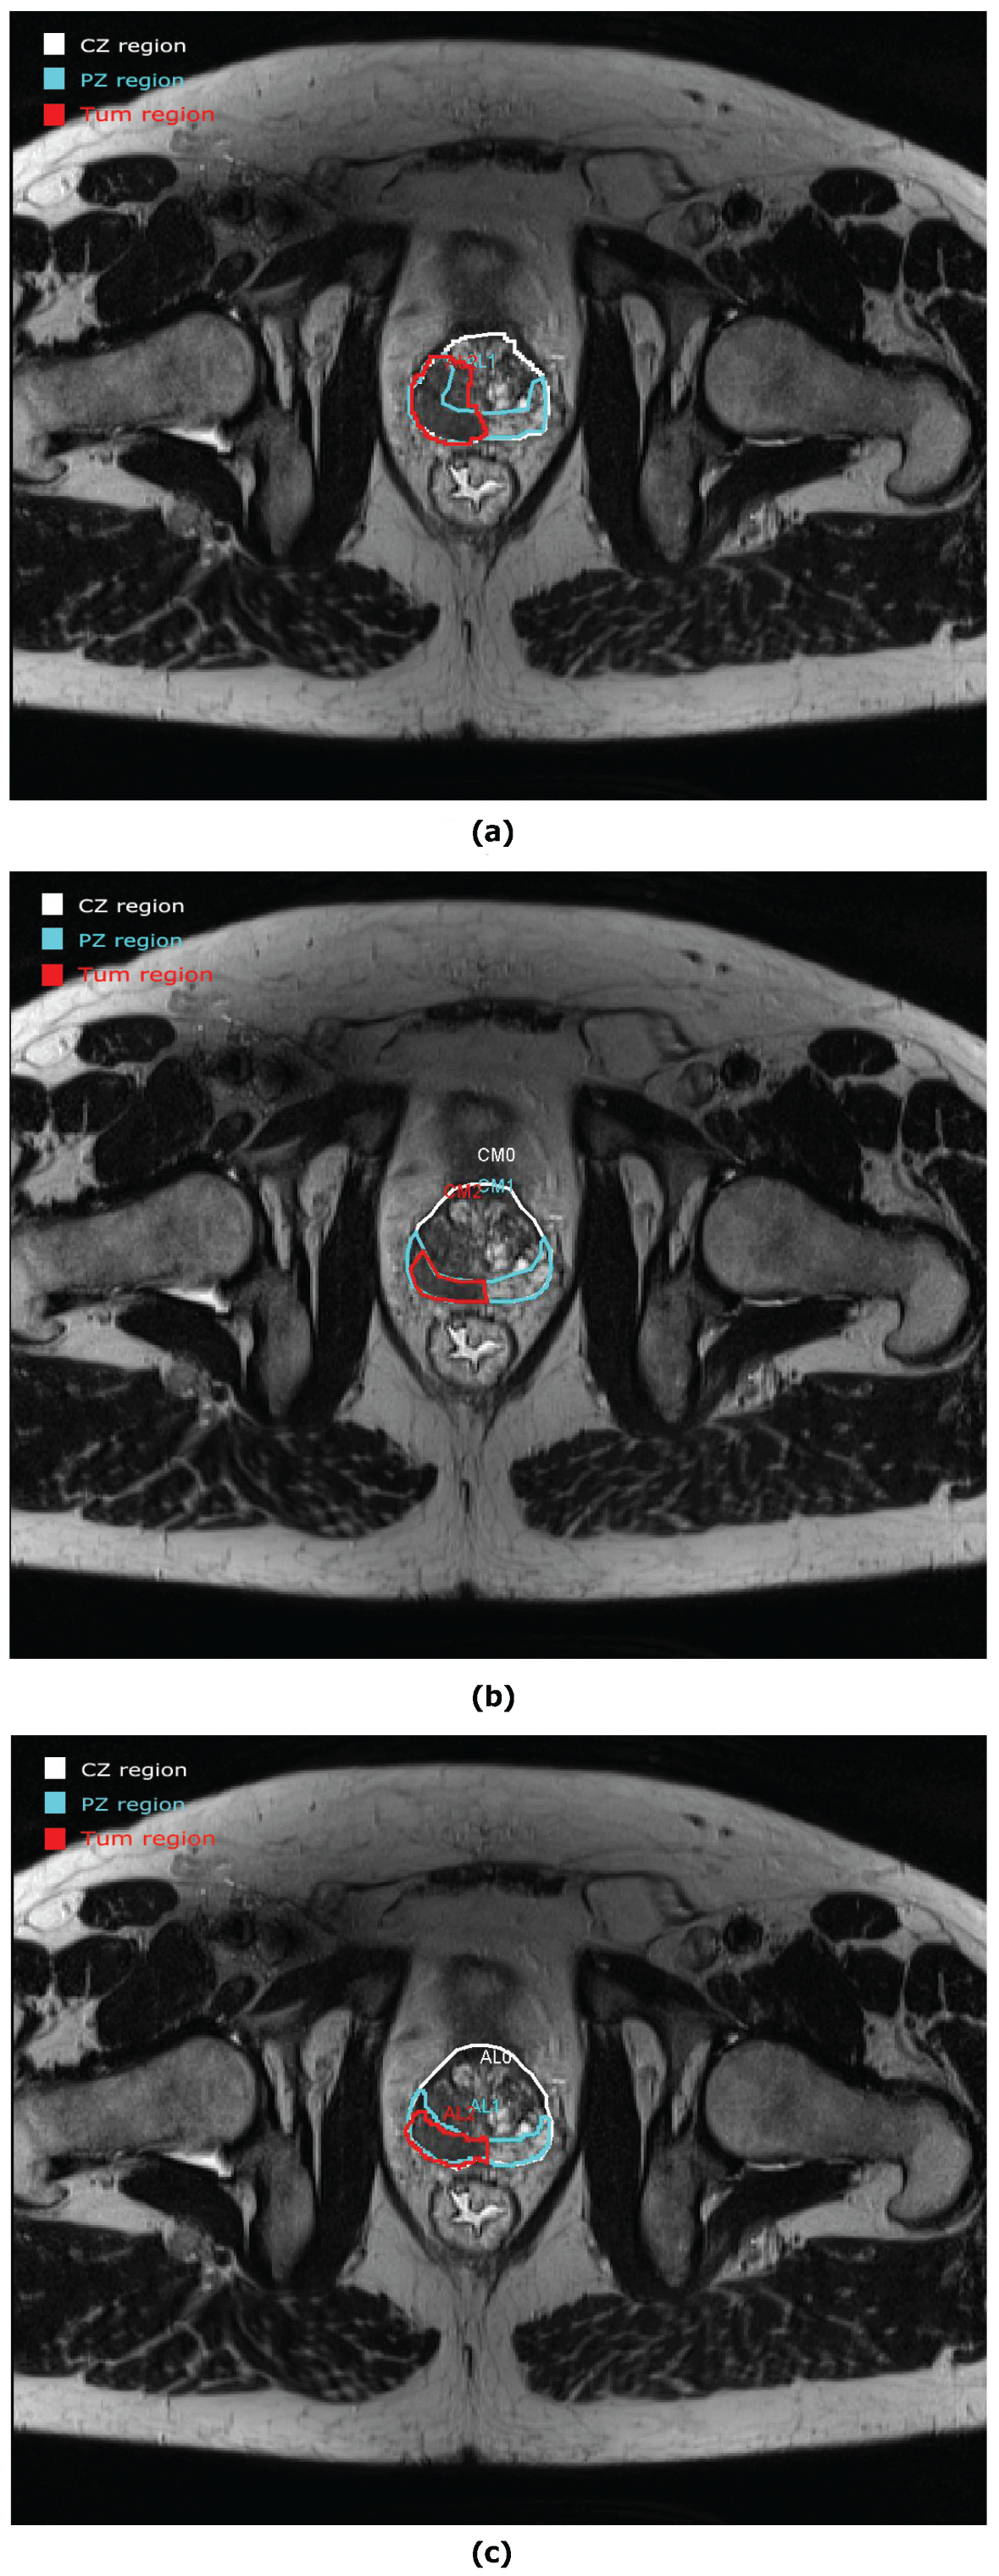

- Mata, C.; Walker, P.; Oliver, A.; Brunotte, F.; Martí, J.; Lalande, A. Prostateanalyzer: Web-based medical application for the management of prostate cancer using multiparametric mr images. Inf. Health Soc. Care 2015, 87, 1–21. [Google Scholar] [CrossRef]

- Romagosa, J.; Benitez, R.; Mata, C. ProstateAnnotation: Web-Based Application for Medical Imaging. IEEE EMBS International Conference on Biomedical and Health Informatics (BHI). 2021. Available online: https://www.bhi-bsn-2021.org/?page_id=2336 (accessed on 29 July 2021).